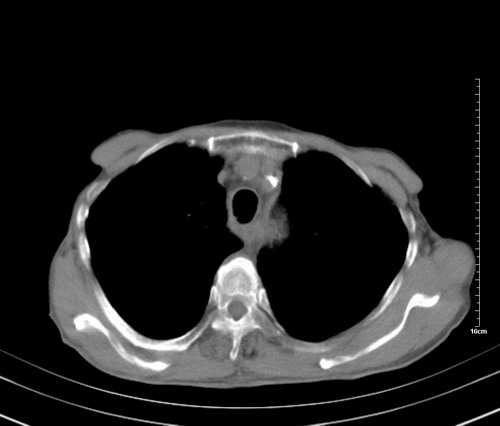

病人,女,79岁,主要因腹疼二月入院,彩超,肝,胆,脾,未见异常,胸透上消化道造影未见异常,化验白细胞增高,内科医生让做胸部ct检查,因为熟人多做了腹部(外科会诊考虑胆囊炎).现ct片如下请假各位战友.

中后纵隔占位,气管、食道受压、变形、移位。恶性可能性大。

考虑:中后纵隔转移瘤可能性大,主动脉硬化。

1 气管旁、隆突下淋巴结明显肿大,肝左叶外侧段低密影,都考虑转移。

后中纵隔团块影,伴气管、食道受压移位,首先考虑转移瘤,肝s5段低密度灶。建议增强检查,另外其结肠是否有问题请提供,右肺部分肺叶局限含气增多,考虑局限肺气肿。

后中纵隔团块影,伴气管、食道受压移位,首先考虑转移瘤,肝表现同11773。